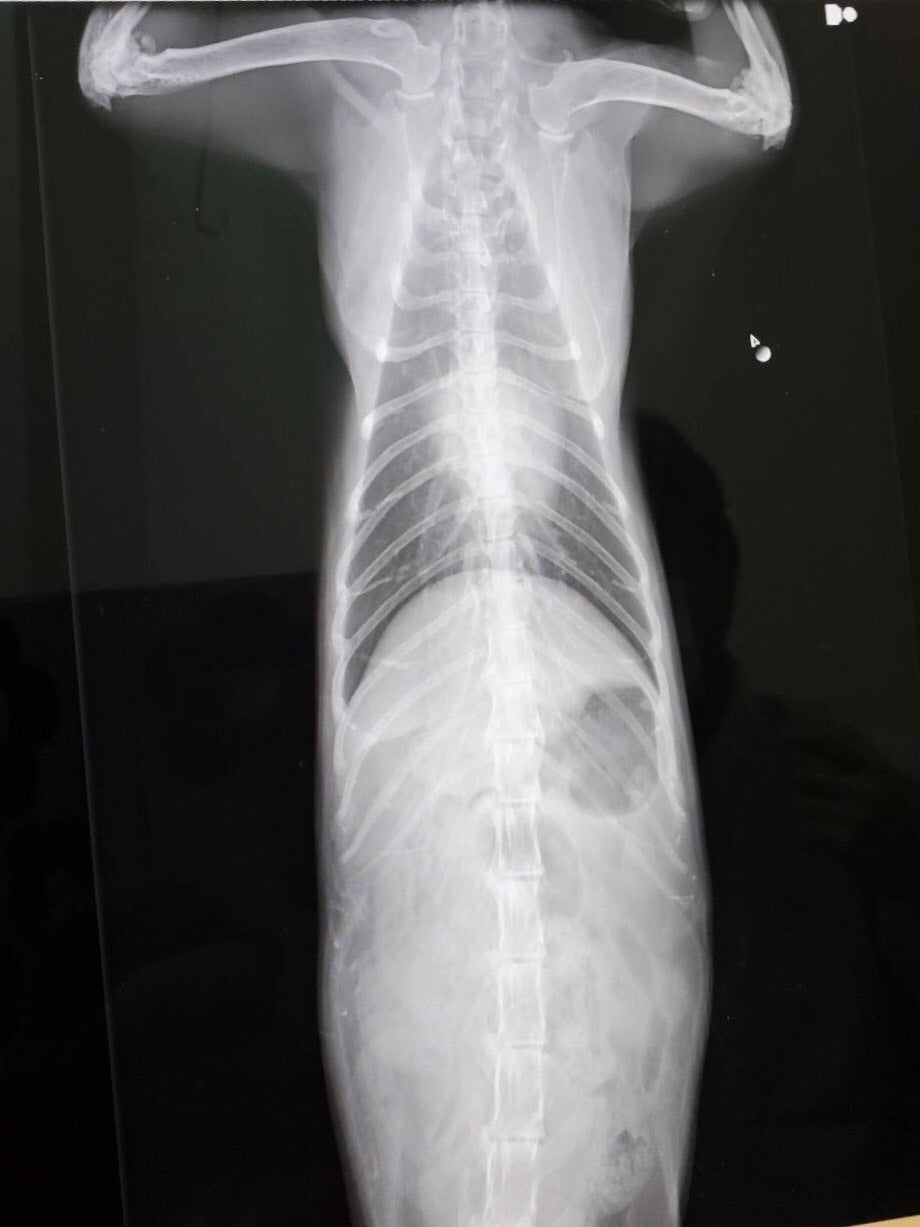

レントゲンで見ると少し肝臓の腫れがあります。

肘の老化もあり痛みがあるはずらしいのですが、感じない猫もいるそうです。」